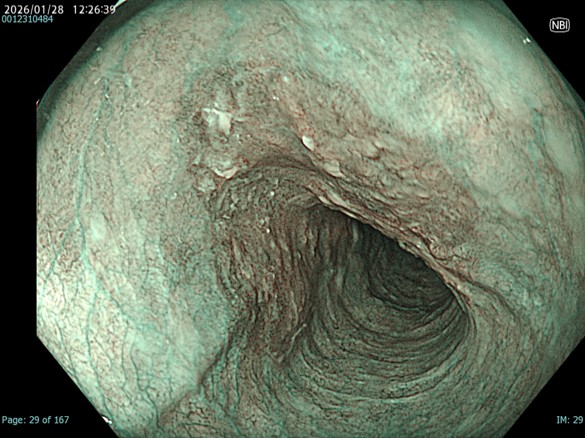

• NBI観察(中遠景)

強調設定:A8

図2

NBIにすることで白色光観察と比較して同部位の粘膜粗造が目立つ。一方で色調変化は軽度でDLも部分的には認識できるが、不明瞭な部分もあり、正確な領域評価が難しい。